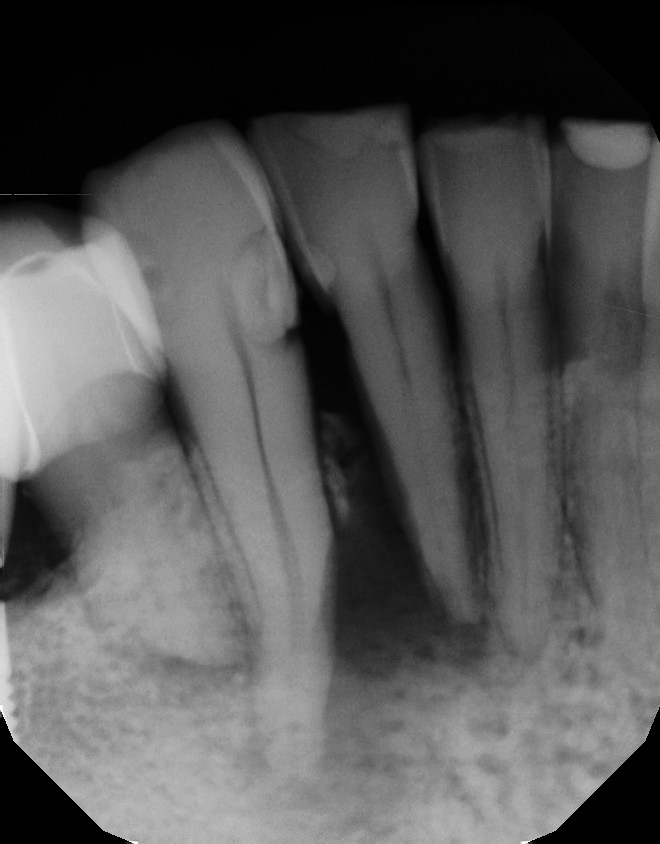

| Necrotic pulp with sinus tract on the buccal of #26. |

| CBCT shows the apical and lateral bone loss on #26 and #27. The lateral bone loss on #27 is also suggestive of a possible root fracture, but since the tooth is necrotic, radiographic appearance alone is not enough evidence to diagnose this with a root fracture. CBCT also shows a 2 canaled root form on #26. |

| There was concern of a possible root fracture, but none could be see internally with microscope. CaOH medicated dressing was placed after initial debridement and NaOCl irrigation. |

| After 3 months in CaOH, we opened and examined again and could find no fractures. Another application of CaOH medicated dressing was placed. |